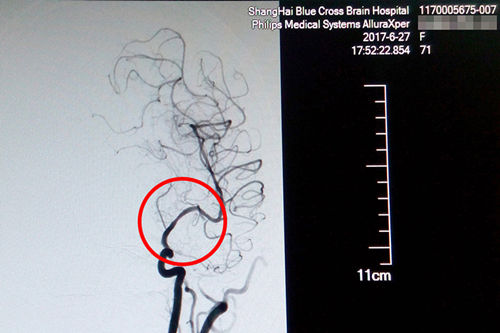

站在手术台前的李主任,表现出的是与平日不同的冷静和沉着。经术中精准测量发现,患者盛阿姨血管狭窄达到了77%,血管非常狭窄,使放置球囊扩张支架的难度更大。好在李主任积累了丰富的DSA手术经验,经过仔细小心的操作,导丝成功地通过了狭窄的血管。李主任用他的“血管艺术”使濒临枯萎的血管重新绽放出了生命的活力,最终原本非常狭窄的血管腔顺利张开了:“……将球囊扩张支架置入狭窄处,观察后准确释放球囊扩张支架,再造行3D造影,显示血管扩张,血流恢复正常。(摘自术后小结)”。

术后DSA影像显示,患者血管狭窄部位血流恢复正常

术后CT影像:支架成功置入

就这样,这台DSA手术又一次获得了成功,术后CT复查无出血,患者恢复情况良好,这才出现了本文开头的感人一幕。原本大面积脑梗、病情凶险的的盛阿姨在李主任和团队的努力下,通过DSA球囊扩张支架置入术,平安度过了生命中的一个转折点。随后,在不到一个月的时间里,她的语言功能已逐渐恢复,四肢肌力已经接近正常水平,目前正在积极接受康复治疗中。